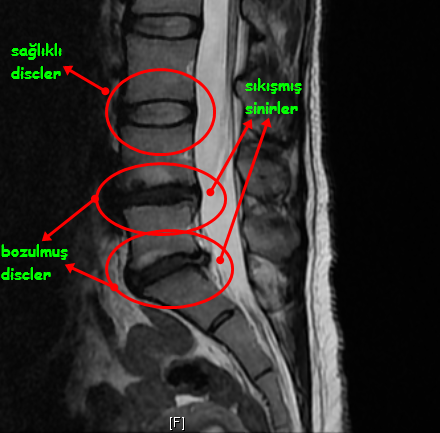

Sağ dizi çok ağrıyordu kasıldığı için yürümekte zorluk çekiyordu. Ameliyatsız bel fıtığı tedavisi. Bel fıtığı ameliyatından sonra hasta iş yaşantısına devam edebilir hayır. L4 l5 s1 bel fıtığı belirtileri piriformis ve çeşitli kalça kasları bu sinirlerden dal aldığı için kalçada ağrı hissedilir yürümede zorluk çekilir ileri derece bel fıtığında görülür oturma pozisyonundan ayağa kalkmak zordur belden başlayıp ayağa kadar uzanan ağrı.

Bel fıtığı tedavisi yöntemleri bel fıtığı tedavisi yöntemleri. Hafif orta ve ileri derece bel fıtığı hakkında bilgiler için hemen bu içeriğimizi inceleyebilir okuyabilir ve bel fıtığı tedavisi için doktorumuza ulaşabilirsiniz. Hastanın kendi kendine yetebilmesinin sağlanması son derece önemlidir. Sizi ve sonuçlarınızı değerlendirdikten sonra sizin için en iyi tedavi yöntemini önerelim.